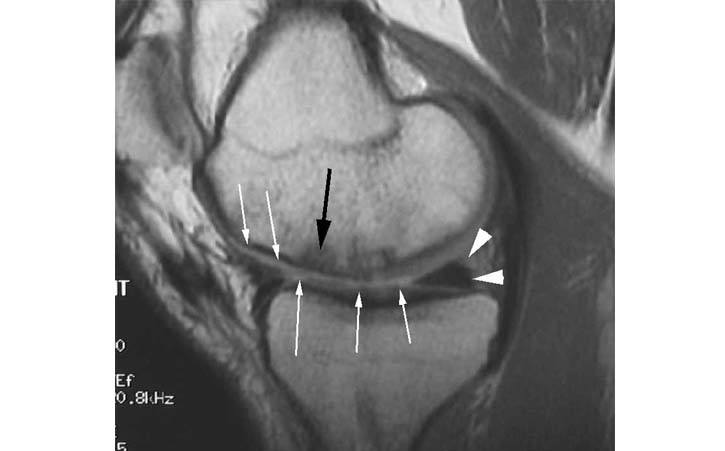

The patient is a 40 year old male with a work related injury to his knee when lifting a 90 lbs suitcase. He had complaints of pain on the inside (medial aspect) of his knee.

2.This sagittal MRI image shows irregularity of the articular cartilage surfaces in the medial femoral condyle and medial tibial plateau (small white arrows). There is also bone edema (black arrow) noted in the femoral condyle consistent with early degenerative changes. The posterior horn of the medial meniscus appears normal (white arrowhead).